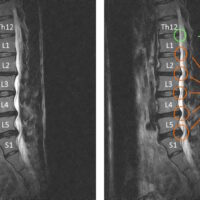

2回目の施術日の前日に整形外科でMRI撮影。かなりひどい腰椎椎間板ヘルニアであることが分かった。

画像を確認したところ、かなり重度の腰椎椎間板ヘルニアが認められました。

緑の〇の部分が正常な状態です。

赤〇の箇所は、椎間板が後方に飛び出ており神経を圧迫している様子がよくわかります。